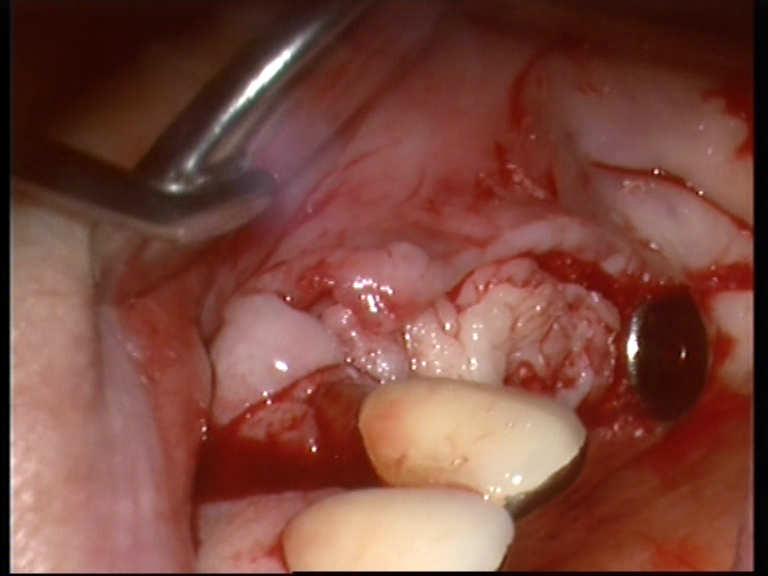

Soft tissue:

Er.CR.:YSGG

Watt: 1.5

Hz: 50

Hard tissue:

Watt: 3.0

Hz: 25